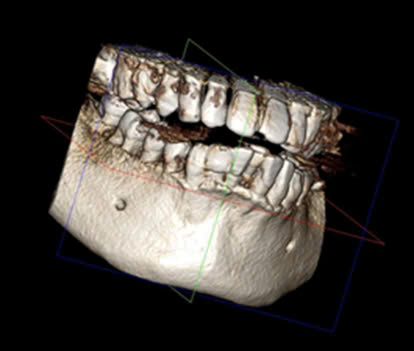

Hình 1. CBCT trước điều trị, bệnh nhân Đ.Q.Q